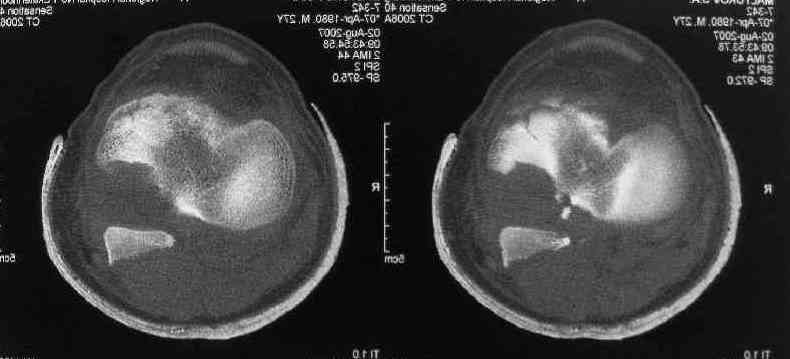

Операция из разряда травматологической "экзотики" прошла успешно. Доступ понравился:анатомичный, хорошая визуализация, удобно работать и оператору и ассистентам. Наложили пневможгут, но воспользовались им только на этапе ревизии сустава. Фрагмент развернулся на 90 град. на 2-ух "жгутах": медиально - сухожилие m.semitendinosus, латерально - задняя крестообразная связка. Мобилизовали,развернули и уложили на место без особого труда. Фиксировали отмоделированной 1/3-трубчатой пластиной. Мениск оказался неповрежден. Сустав стабилен. Обошлись без

иммобилизации, планируем начать ранние движения. Остальное на фото, дополнительно приложены корональные срезы КТ.